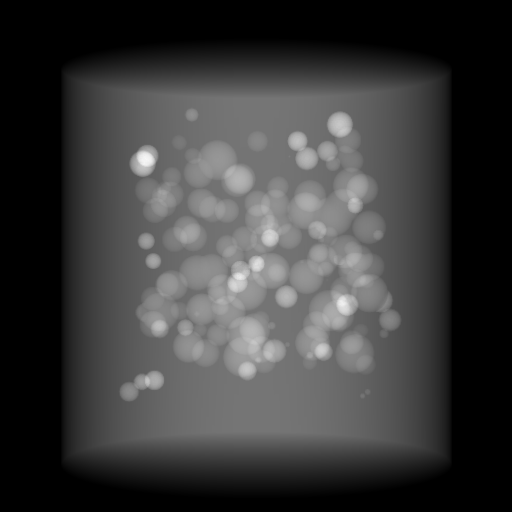

Figure 6: An example for perspective deformation learning from dual complementary views: (a) the orthogonal projection of the 3D bead phantom from the 0superscript00^{\circ} view; (b) the perspective projection from the 0superscript00^{\circ} view; (c) the difference image between (b) and (a); (d) the perspective projection from the 180superscript180180^{\circ} view; (e) the difference image between (d) and (b); (f) the RGB stack of the 0superscript00^{\circ} and 180superscript180180^{\circ} perspective projection images, where the magenta and green areas correspond to the positive (bright) and negative (dark) areas in (e). The intensity range [0, 11] is converted to [0, 255] for visualization.

The orthogonal and perspective projection images of the same 3D bead phantom in a complementary view setting are displayed in Fig. 6. Fig. 6(c) shows the perspective deformation, which is the difference between the perspective projection (Fig. 6(b)) and the orthogonal projection (Fig. 6(a)) from the 0superscript00^{\circ} view. Fig. 6(c) clearly demonstrates that the magnitude of perspective deformation increases from the center outwards radially. The 180superscript180180^{\circ} perspective projection image is displayed in Fig. 6(d) and its difference with respect to the 0superscript00^{\circ} perspective projection is displayed in Fig. 6(e). Fig. 6(e) is similar to Fig. 6(c) in bead areas, which illustrates that the deviation between two complementary views has strong correlation to perspective deformation. To integrate such dual-view information, like Fig. 5(d), we convert the perspective projections images from the 0superscript00^{\circ} and 180superscript180180^{\circ} views to a 3-channel RGB image in Fig. 6(f). The red and blue channels use images from the 0superscript00^{\circ} view, while the green channel uses images from the 180superscript180180^{\circ} view. In the RGB images, the color reveals the intensity difference between the 0superscript00^{\circ} and 180superscript180180^{\circ} perspective projection images. Grey areas contain close intensity values from both views. Instead, magenta and green areas indicate larger intensity values from the 0superscript00^{\circ} and 180superscript180180^{\circ} views respectively, where perspective deformation correction is necessary. They correspond to the positive (bright) and negative (dark) areas in the difference image in Fig. 6(e). In Fig. 6(f), the magenta beads and their corresponding green beads are located close to each other, which allows a network with limited receptive field size to capture bead-to-bead (point-to-point) dependency.